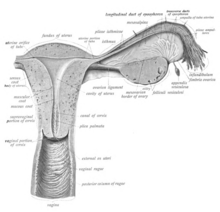

Layers, regions and histology

The wall of the vagina from the lumen outwards consists firstly of a mucosa of non-keratinized stratified squamous epithelium with an underlying lamina propria of connective tissue, secondly a layer of smooth muscle with bundles of circular fibers internal to longitudinal fibers, and thirdly an outer layer of connective tissue called the adventitia. Some texts list four layers by counting the two sublayers of the mucosa (epithelium and lamina propria) separately.[17][18] The lamina propria is rich in blood vessels and lymphatic channels. The muscular layer is composed of smooth muscle fibers, with an outer layer of longitudinal muscle, an inner layer of circular muscle, and oblique muscle fibers between. The outer layer, the adventitia, is a thin dense layer of connective tissue, and it blends with loose connective tissue containing blood vessels, lymphatic vessels and nerve fibers that is present between the pelvic organs.[14][18][19]

The mucosa forms folds or rugae, which are more prominent in the caudal third of the vagina; they appear as transverse ridges and their function is to provide the vagina with increased surface area for extension and stretching. Where the vaginal lumen surrounds the cervix of the uterus, it is divided into four continuous regions or vaginal fornices; these are the anterior, posterior, right lateral, and left lateral fornices.[12][13] The posterior fornix is deeper than the anterior fornix.[13] While the anterior and posterior walls are placed together, the lateral walls, especially their middle area, are relatively more rigid; because of this, the vagina has a H-shaped cross section.[13] Behind, the upper one-fourth of the vagina is separated from the rectum by the recto-uterine pouch. Superficially, in front of the pubic bone, a cushion of fat called the mons pubis forms the uppermost part of the vulva.

Supporting the vagina are its upper third, middle third and lower third muscles and ligaments. The upper third are the levator ani muscles (transcervical, pubocervical) and the sacrocervical ligaments; these areas are also described as the cardinal ligaments laterally and uterosacral ligaments posterolaterally. The middle third of the vagina concerns the urogenital diaphragm (also described as the paracolpos and pelvic diaphragm). The lower third is the perineal body; it may be described as containing the perineal body, pelvic diaphragm and urogenital diaphragm.[12][20]

For blood and nerve supply, relevant arteries are the cervicovaginal (the uterine cervix and the vagina) branch of the uterine artery, the vaginal artery, middle rectal artery, and the internal pudendal artery. The veins are connected by anastomosis (the connection of separate parts of a branching system to form a network), resulting in the formation of the anterior and posterior azygos (unpaired) arteries. The nerve supply of the vagina is provided by the sympathetic and parasympathetic areas of the pelvic plexus, with the pudendal nerve supplying the lower area.[13]